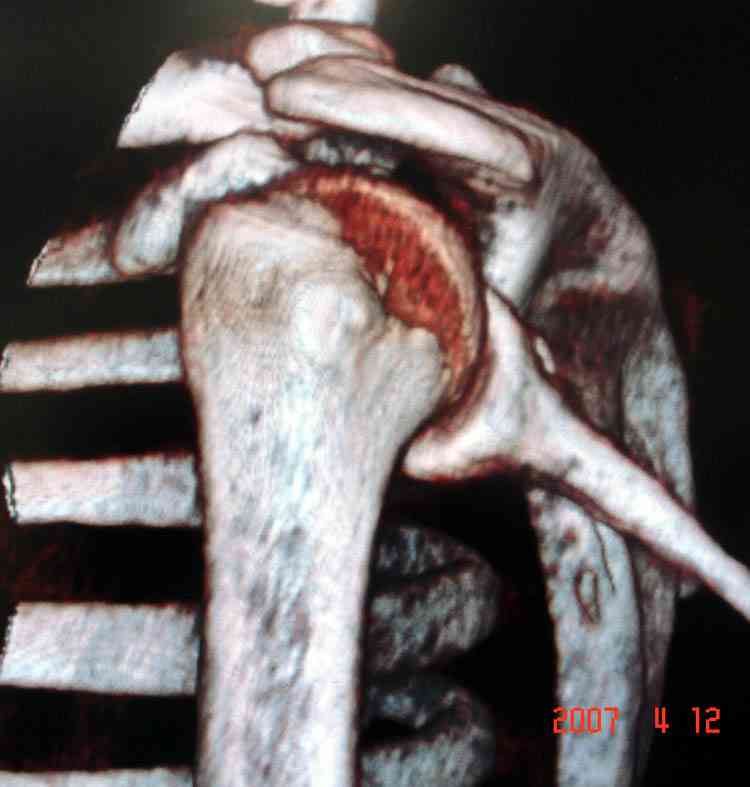

На снимке (№6 компьютерная томограмма и 3D №7) перелом клювовидного отростка.

Передним дельтопекторальным Bankart доступом намного легче провести фиксация отростка, но тогда репозиция и фиксация колонн затрудняется, поэтому был применен стандартный Judet задний доступ.

Репозицию смогли сделать пальцами через щель между

шейкой и телом лопатки (последний 3D снимок)

Двумя шурупами сзади на пластине (вместе шайбы)

провели удержание репозиции, а фиксацию провели

следующим косым шурупом.

Последующие этапы на снимках.